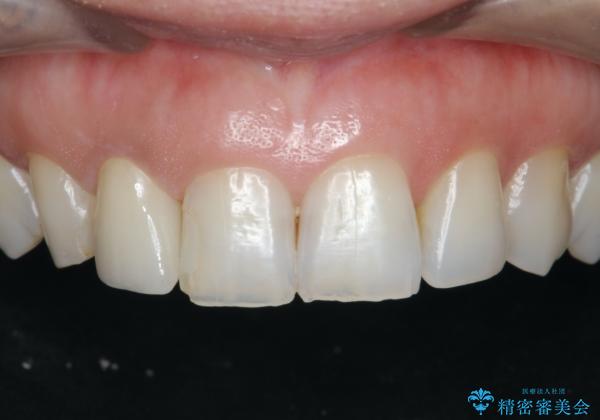

- 前歯の付近、歯ぐきを押すと違和感を感じその改善を求めて来院されました。

X線検査の結果、失活(感染根管)であることが判明したので、感染根管治療後セラミック補綴を計画します。

セラミック治療を行う前にきっちりと根管治療を行うことが長期的に持つ可能性を高めます。